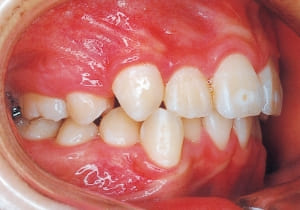

2 After Phase 2 Treatment 6-6-’94

The first phase of treatment involved extracting the left and right maxillary deciduous canines. The space created was used to forcibly retract the four anterior teeth, thereby aiming to improve lip closure function (6–9, 11). Morphological changes suggest that lip function differed before and after treatment (6, 9). Subsequently, the first premolars erupted, but extraction is planned to secure space for canine eruption (10). A Class II molar relationship remains, but the significant overjet has improved (11).

In the maxilla, insufficient space for canine eruption was inevitable, necessitating extraction as part of the treatment plan. The maxillary first premolars on both sides were extracted during routine observation to create space for canine eruption (14). Eventually, the canines erupted and settled into relatively favorable positions (15,19,20). In the mandibular dentition, crowding was also present, leading to extraction of the mandibular first premolars on both sides. Treatment with full bracket was then initiated (17).